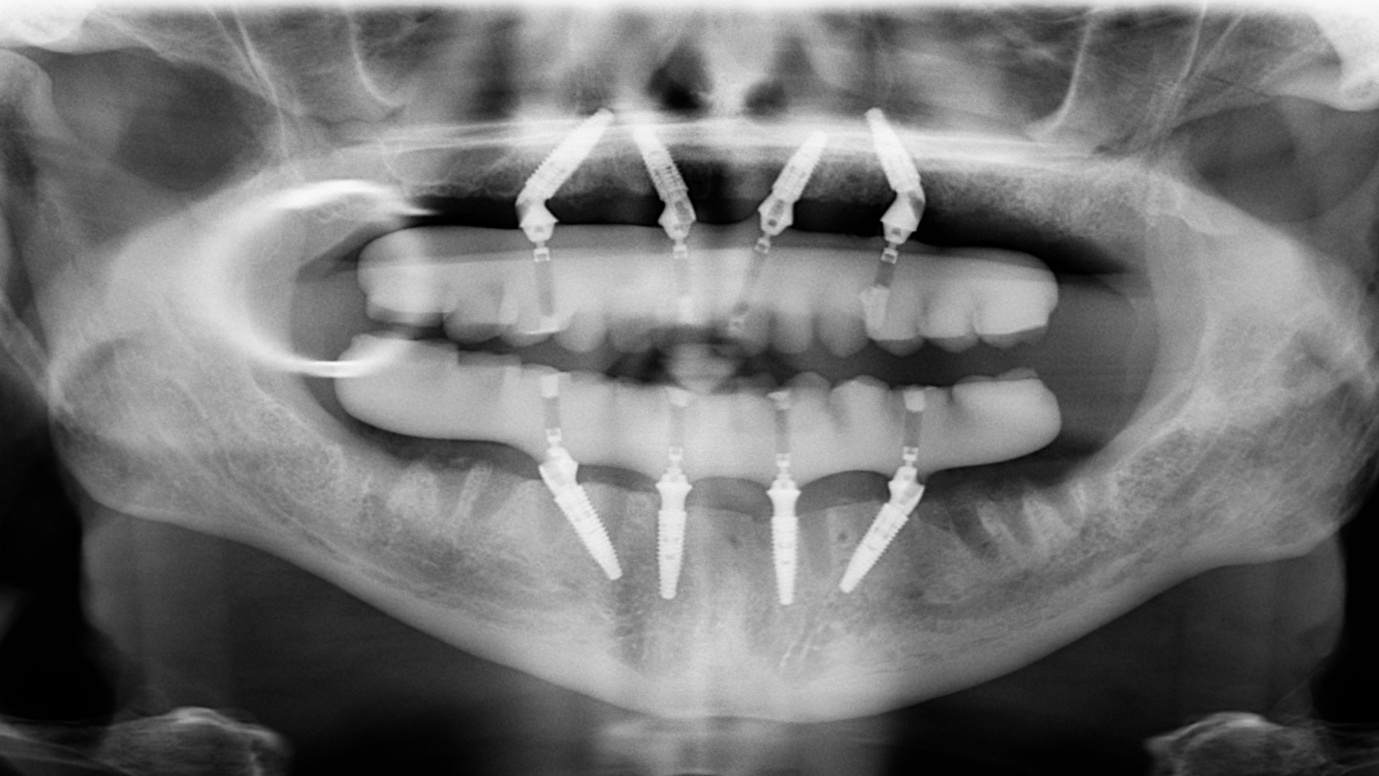

Image caption 2: OPG view showing implant-supported full arch rehabilitation in the upper and lower jaws.

Following treatment, the patient received fixed upper and lower implant-supported acrylic titanium restorations.

The completed rehabilitation improved full arch support, stability, function, and smile aesthetics. Treatment also addressed the poor prognosis associated with the remaining teeth present before treatment.